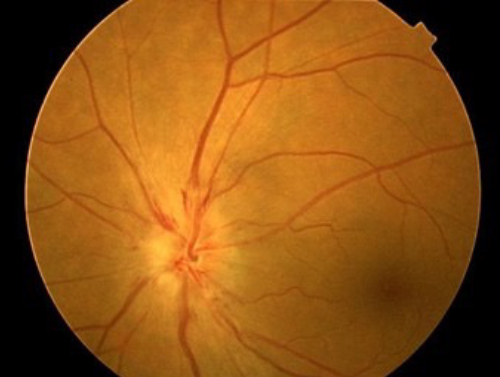

正常視神経乳頭

緑内障による視神経乳頭陥凹

緑内障

緑内障とは

眼の硬さが固く(眼圧の上昇)なることにより視神経や神経線維が障害される疾患です。

40歳以上の日本人の緑内障有病率は約20人に1人です。わが国の成人失明原因の第1位です。

症状

徐々に視野が狭くなっていきますが、初期には反対眼の視野で補われるので、自覚症状が少なく、気づかないうちに進んでしまうことが多いのが特徴です。検診で緑内障の疑いを指摘された方は、どうぞお気軽にご相談ください。

急性発作を起こすタイプは緊急処置を要する病気です。慢性的に進行する緑内障や続発緑内障は早期発見、早期治療で病気の進行を抑えることができます。

治療

緑内障の治療の目的は、眼圧を下げて視神経へのダメージを抑えることです。

病気の進行を止めることはできますが、一度失った視野は元に戻せませんので早期発見、早期治療、継続治療が大切になります。

初期治療としては、点眼薬による薬物治療または低侵襲レーザー治療(SLT:選択的線維柱帯形成術)を行います。

保護的治療で眼圧のコントロールが得られない場合は、手術を行います。

流出路再建術や濾過手術に加え、近年では、MIGS(低侵襲緑内障手術)と呼ばれる手術を行います。

緑内障の病型や視野進行の程度に応じて当センターでもマイクロフックを用いた線維柱帯切開術やiStentW®手術を行っています。

Express®シャント手術に加え比較的新しいブレブ手術であるプリザーフロ®マイクロシャント手術についても、適応がある患者様に対して治療を行います。